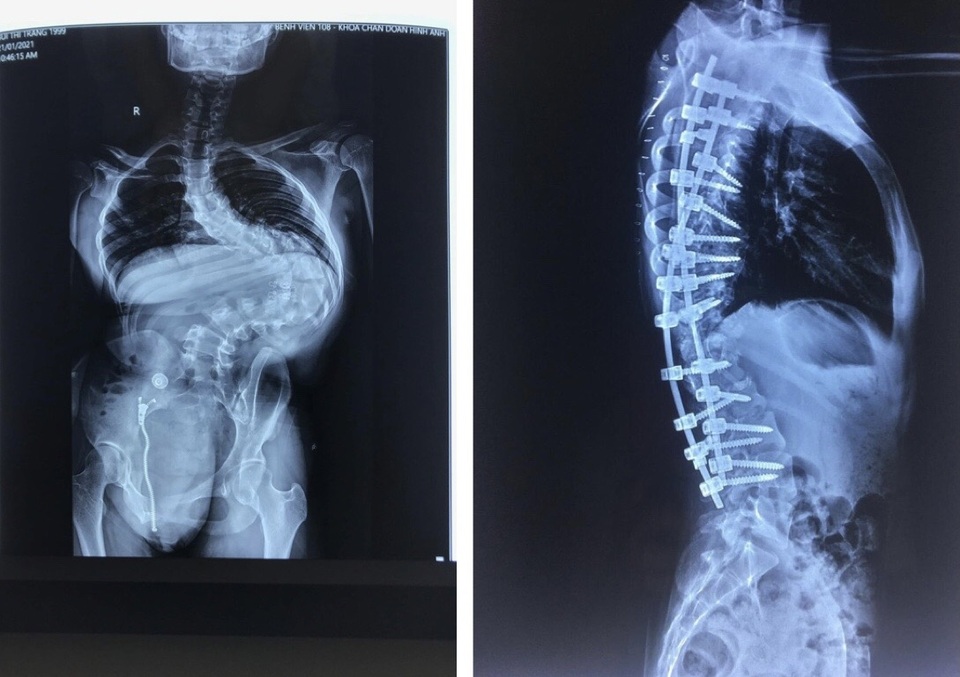

Sau khi thực hiện các xét nghiệm và hội chẩn, Khoa Phẫu thuật Chỉnh hình cột sống nhận thấy đây là một ca cong vẹo rất lớn, có thể là lớn nhất từ trước tới nay (cong vẹo T7L3 135 độ). Hơn nữa bệnh nhân 22 tuổi, nên việc phẫu thuật và nắn chỉnh biến dạng khó, mang nhiều yếu tố nguy cơ và rủi ro, đặc biệt là có thể gây liệt và thậm chí là tử vong trên bàn mổ.

Theo đó, ở lần phẫu thuật thứ 2, các bác sĩ đã cố định, nắn chỉnh biến dạng bằng các dụng cụ, đinh vít. Ca mổ diễn ra gần 8 tiếng, kết quả khá toàn vẹn.

Sau mổ, bệnh nhân phục hồi khá tốt, khối "mai rùa" đã biến mất, cao thêm 20 cm và có thể đi lại nhẹ nhàng.